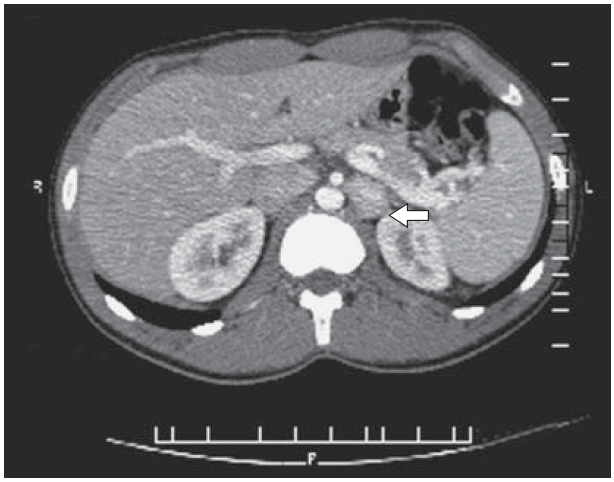

16. Рис. 4. КТ больного с параганглиомой. | |